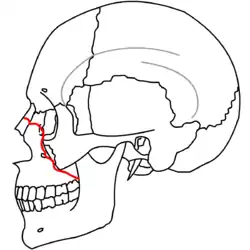

At the beginning of the 20th century, René Le Fort mapped typical locations for facial fractures; these are now known as Le Fort I, II, and III fractures (right).[7] Le Fort I fractures, also called Guérin or horizontal maxillary fractures,[14] involve the maxilla, separating it from the palate.[15] Le Fort II fractures, also called pyramidal fractures of the maxilla,[16] cross the nasal bones and the orbital rim.[15] Le Fort III fractures, also called craniofacial disjunction and transverse facial fractures,[17] cross the front of the maxilla and involve the lacrimal bone, the lamina papyracea, and the orbital floor, and often involve the ethmoid bone,[15] are the most serious.[18] Le Fort fractures, which account for 10–20% of facial fractures, are often associated with other serious injuries.[15] Le Fort made his classifications based on work with cadaver skulls, and the classification system has been criticized as imprecise and simplistic since most midface fractures involve a combination of Le Fort fractures.[15] Although most facial fractures do not follow the patterns described by Le Fort precisely, the system is still used to categorize injuries.[5]

| Le Fort III fractures | |